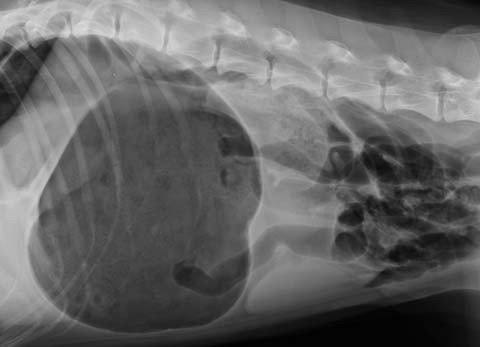

Nella torsione gastrica lo stomaco del cane si torce sul suo asse. In questo caso vengono occlusi i vasi sanguigni uscenti ed entranti, nonché le vie di entrata e di uscita dello stomaco. Questa occlusione dei vasi sanguigni provoca un collasso cardiocircolatorio. Lo strozzamento delle vie di entrata e di uscita dello stomaco provoca una dilatazione dello stesso, il cane è gonfio e ha un addome durissimo.

Tipico sintomo 1 o 2 ore dopo i pasti è l'addome gonfio e dolorante. L'animale è molto irrequieto e cerca di vomitare, senza riuscirci. Col passare dl tempo l'addome si gonfia sempre di più. L'animale diventa apatico.